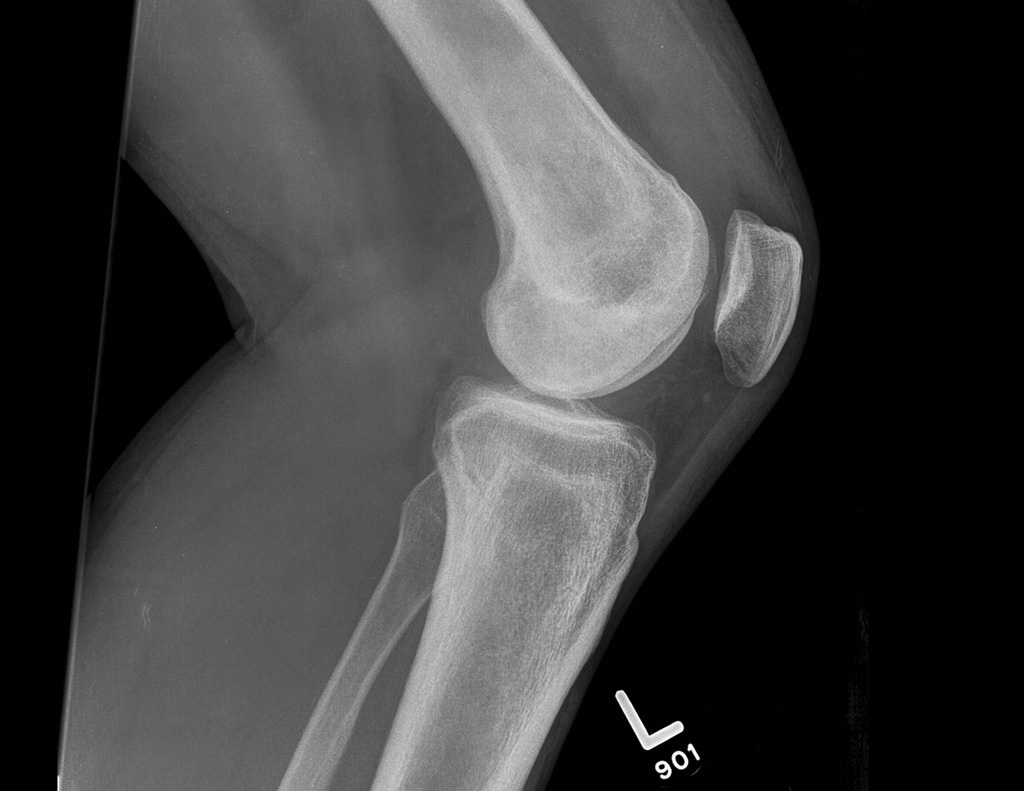

The knee is be divided into two parts, the joint between the upper and lower leg (the femur and tibia), called the tibiofemoral joint, and the joint between the upper leg and the knee cap (the femur and patella), called the patellofemoral joint. Both of these joints can be vulnerable to injury, with each often displaying their own distinct pattern of signs and symptoms.

• Osteoarthritis of the tibiofemoral joint: degeneration of the cartilage which lines the bones in the joint

• Osteoarthritis of the patellofemoral joint: degeneration of the cartilage which lines the bones in the joint

• Patella Dislocation: when the kneecap is pulled completely out from its groove within the femur